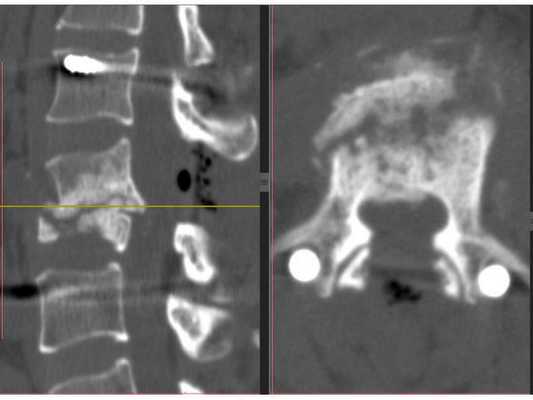

По результатам КТ шейного отдела позвоночника травматической патологии не выявлено, отмечается сглаженность шейного лордоза, спондилёз (естественное изнашивание и старение позвонков с формированием нежелательных костных разрастаний), наиболее выраженный в позвонках C5-C6. МРТ исследование по техническим причинам выполнено на следующий день: выявлен стеноз (сужение) позвоночного канала с уровня C3-C4 до уровня C5-С6 с формированием очагов миелопатии (поражения спинного мозга) с уровня C3 до C6; отмечается "свечение" тела С5 позвонка, свидетельствующее о наличии гемокомпонента в ячейках губчатой костной ткани. Предположительно, гемокомпонент появился вследствие компрессии тела С5 позвонка в момент травмы.

МРТ шейного отдела позвоночника: в Т2-режиме видны миелопатические очаги в сегменте С3-С6 на фоне абсолютного стеноза с уровня С3-С4 до С5-С6